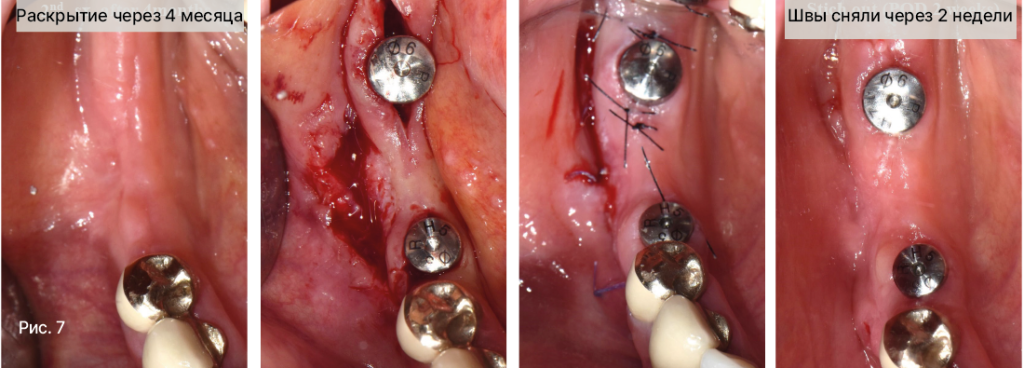

Рис. 7. Раскрытие имплантатов с апикальным смещением лоскута Р.8 .jpg

• Апикальное смещение лоскута с увеличением глубины преддверия может улучшить состояние мягких тканей в области постоянного протеза с опорой на имплантаты.